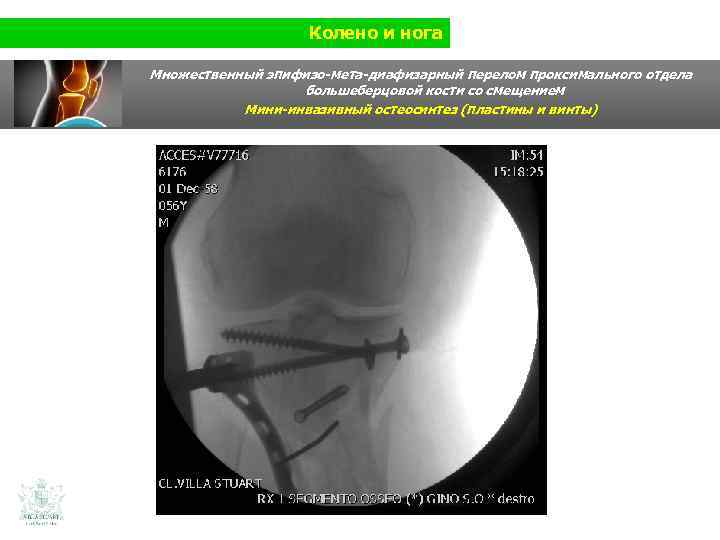

Колено и нога Множественный эпифизо-мета-диафизарный перелом проксимального отдела большеберцовой кости со смещением Мини-инвазивный остеосинтез (пластины и винты)